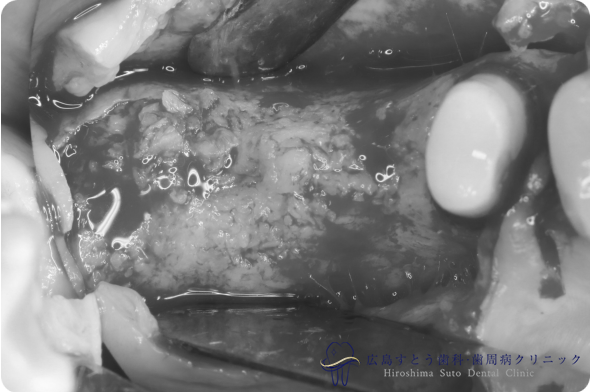

術中(手術中の写真)

手術中の状態:骨移植前

骨移植後6ヶ月

右下の手術中の状態:骨移植前

右下の手術中の状態:骨移植後